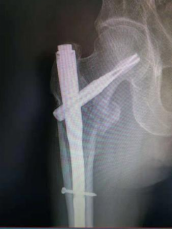

1.股骨粗隆间骨折—PFNA内固定术(微创)